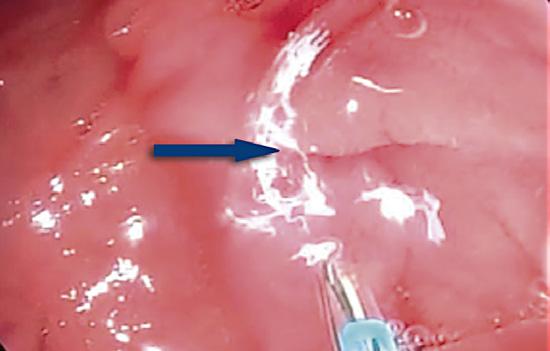

Una complicación infrecuente del páncreas ectópico

13. Distrofia quística en páncreas ectópico duodenal

es la distrofia quística, que se postula representa la dilatación tubular y sacular de los conductos en el interior del tejido heterotópico (Figura 13). Es posible hallarla en el estómago y sobre todo en la 2° porción del duodeno, donde puede conducir a una pancreatitis paraduodenal, también denominada pancreatitis del surco.21,22

A) Resonancia magnética, secuencia T2, plano axial. Las flechas señalan múltiples imágenes quísticas (redondeadas, hiperintensas en T2) vinculadas al páncreas ectópico, el cual se ubica en la pared medial de la 2° porción del duodeno (cabeza de flecha). B) Resonancia magnética, secuencia T2, plano coronal. El surco pancreaticoduodenal se encuentra ensanchado y se evidencian cambios de fibrosis relacionados a la distrofia quística, hallazgos compatibles con pancreatitis paraduodenal.